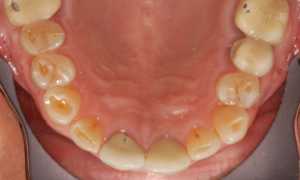

Фото 2. Локальный пародонтит. Воспалены несколько зубов, в области воспаления наблюдается кровотечение.